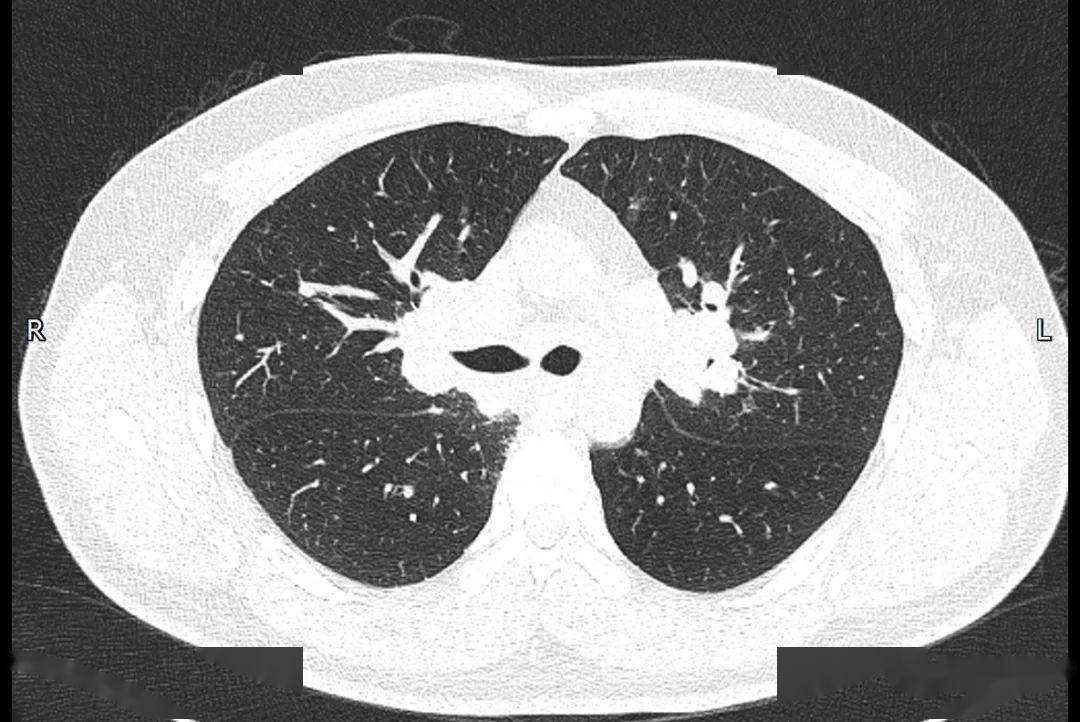

肺结节病

结节病CT